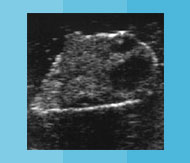

Besamung Verhalten Verhalten in der Vorbrunst In der Vorbrunst beginnt das Tier unruhig zu werden (Flehmen, Kopf auflegen). Brünstig werdende Tiere legen oft den Schwanz zur Seite, insbesondere, wenn sie von anderen Tieren beschnuppert werden. Für eine Besamung ist es zu früh, aber man muss gut beobachten! Verhalten in der Brunst Zu Brunstbeginn kann es rund um die brünstig werdende Kuh sehr unruhig werden. Besonders auf der Weide ist das gut sichtbar. Mitte der Brunst: Die Kuh duldet andere Kühe, wenn diese ihr aufspringen. Sie zeigt den Duldungsreflex. Für eine Besamung ist es noch zu früh! Aber die Kuh kann bereits beim Besamer angemeldet werden. Im Stall kann man hochbrünstige Tiere am stieren Blick, gestellten Ohren und durchgekrümmten Rücken manchmal gut erkennen. Verhalten in der Nachbrunst Jetzt is der ideale Besamungszeitpunkt! Das Tier wird wieder ruhiger und duldet andere Tiere nicht mehr beim Aufsprungversuch. Aber: Beim Abbluten ist es zu spät für die Besamung! Verhalten in der Zwischenbrunst In der Zwischenbrunst verhalten sich die Tiere unauffällig. 2-3 unruhige Phasen von einigen Stunden sind möglich. Eine Besamung macht hier keinen Sinn! Eierstock Eierstock in der Vorbrunst Der Gelbkörper bildet sich zurück. Das dominate Eibläschen hat einen Durchmesser von gut 1cm. Das Eibläschen ist glatt und prall („uhrglasartig“). Der Eierstock in der Brunst Das Eibläschen wächst in kurzer Zeit heran und ist prall. Der Gelbkörper von der letzten Brunst kann noch spürbar sein. Das Eibläschen erreicht einen Durchmesser von ca. 1.5 bis 2 cm und wird weicher. Jetzt hat das Eibläschen seine maximale Grösse erreicht. Kurz bevor es springt, wird es weich. Der Eierstock in der Nachbrunst Zu Beginn der Nachbrunst springt das Eibläschen. Das Eibläschen wird vom Eileitertrichter aufgefangen. Im Eileiter findet die Befruchtung durch den Samen statt. Der Eierstock in der Zwischenbrunst Der Gelbkörper hat oft eine Form wie ein Champagnerzapfen. Während eines Zyklus können sich 1-2 Eibläschen auf dem Eierstock an- und wieder zurückbilden. Der Gelbkörper bildet sich zurück, wenn von der nichtträchtigen Gebärmutter Prostaglandin gebildet wird. Gebärmutter & Scheide Gebärmutter u. Scheide in der Vorbrunst Die Spannung in der Gebärmuttermuskulatur nimmt zu. Der Muttermund beginnt sich zu öffnen. Die Scheidenschleimhaut wird wieder feucht und rötet sich. Gebärmutter u. Scheide in der Brunst Die Gebärmuttermuskulatur zieht sich in der Brunst maximal zusammen. Die Gebärmutter ist daher klein und fest. Die Schleimhaut in der Scheide erscheint blassrosa und feucht und der Muttermund kann deutlich offen sein. Fadenziehender klarer Schleim kommt aus der Scheide. Gebärmutter u. Scheide in der Nachbrunst Die Muskulatur der Gebärmutter entspannt sich. Das Abbluten kann als guter Anhaltspunkt auf dem Brunstkalender festgehalten werden. Die Schwellung der Schamlippen geht zurück. Gebärmutter u. Scheide in der Zwischenbrunst Die Muskulatur der Gebärmutter ist entspannt und wenig kontrahiert. Der Muttermund ist fest verschlossen und die Scheidenschleimhaut ist wenig feucht und blass. Die Schamlippen sind gefältelt. Hormone Hormone in der Vorbrunst Hormone aus dem Zwischenhirn (GnRH) und der Hirnanhangsdrüse (FSH) werden in die Blutbahn abgegeben. Das follikelstimulierende Hormon FSH bewirkt die letzte Reifung des dominanten Eibläschens. Das dominante Eibläschen produziert das Brunsthormon (Östrogen). Hormone in der Brunst Das Brunsthormon wird vom Eibläschen produziert. Das Brunsthormon ist verantwortlich für das typische Verhalten der Kuh in der Brunst und die sichtbaren Veränderungen am Geschlechtstrakt. Der Anstieg des luteinisierendem Hormons LH führt zum Eisprung am Ende der Hauptbrunst oder bereits zu Beginn der Nachbrunst. Hormone in der Nachbrunst Das luteinisierende Hormon bewirkt den Eisprung und die Bildung von Gelbkörpergewebe. Die Produktion vom Trächtigkeitshormon beginnt. Der Spiegel vom Brunsthormon ist wieder tief. Hormone in der Zwischenbrunst Der Gelbkörper bildet im Zyklus während ca. 14 Tagen das Trächtigkeitshormon Progesteron. Bei einer Trächtigkeit bildet die Gebärmutter dank Signal des Embryos um den 16. Zyklustag kein Prostaglandin F2alpha und der Gelbkörper bleibt bestehen. Ohne Befruchtung bildet die Gebärmutter Prostaglandin F2alpha, der Gelbkörper geht zu Grunde und ein neuer Zyklus beginnt. Bedienungsanleitung Vorbrunst Brunst Nachbrunst Zwischenbrunst